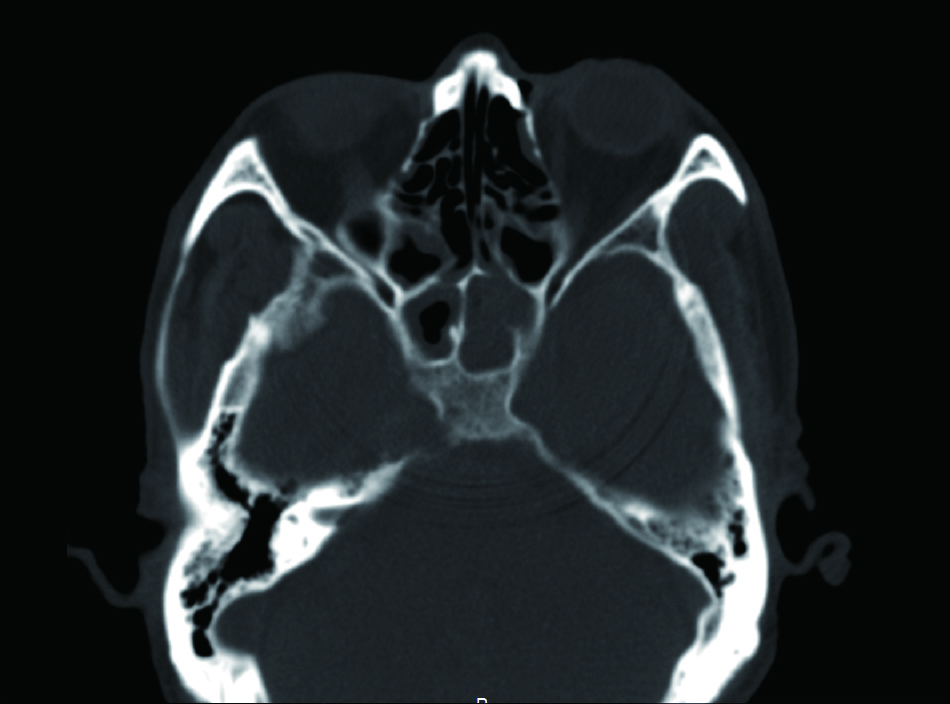

1 资料与方法病例1,患者男性,66岁,因头痛3周,复视1周入院。患者3周前起右侧太阳穴针刺样疼痛,影响睡眠。2周前出现咽痛鼻塞流涕及双耳听力下降,伴有右侧额部皮肤红疹,上述症状在当地医院治疗后减轻。1周前出现复视,当地医院治疗后症状无好转,诊断:颅内感染,多颅神经麻痹转来本院急诊。查体:神清,面部可见散在淡色丘疹,以右侧前额为主,右眼外展受限,面部痛触觉无殊,四肢肌力5级,病理反射阴性。脑脊液生化常规示:潘氏试验阳性,有核细胞970/μL;血沉28.00 mm/h,C反应蛋白14.1 mg/L。增强头颅MR提示两侧海绵窦增粗增宽,考虑炎症,并见双侧筛窦上颌窦蝶窦炎(图 1)。予头孢曲松钠2.0 g静脉注射抗感染治疗。治疗2周后头痛明显减轻,但复视症状无好转。复查血常规正常,C反应蛋白正常范围,血沉28.00 mm/h,脑脊液生化及常规正常范围。复查头颅增强MR提示病变范围较前无缩小。鼻窦CT提示双侧蝶窦炎症较前加重(图 2)。建议患者行鼻内镜下蝶窦手术。患者自觉症状减轻拒绝手术,要求出院。出院后在外院继续头孢曲松钠抗感染治疗。治疗10 d后因头痛复视症状无改善,并出现面颊部感觉减退再次入院。入院后查血常规,C反应蛋白正常,血沉28.00 mm/h,脑脊液潘氏试验阳性,细胞数量继续减少至60/μL。继续抗感染治疗。再次头颅MR及鼻窦CT复查提示海绵窦及蝶窦内病变较前范围增大(图 3),经多学科讨论,转本科行视频内镜下双侧蝶窦开放术。术后第三天鼻腔填塞物完全抽除后头痛症状明显缓解,术后6 d出院,头痛症状消失,复视仍存,出院后继续抗感染治疗,定期门诊复诊,术后6个月,复视症状消失。

| 图 1 双侧海绵窦增宽,右侧明显 |